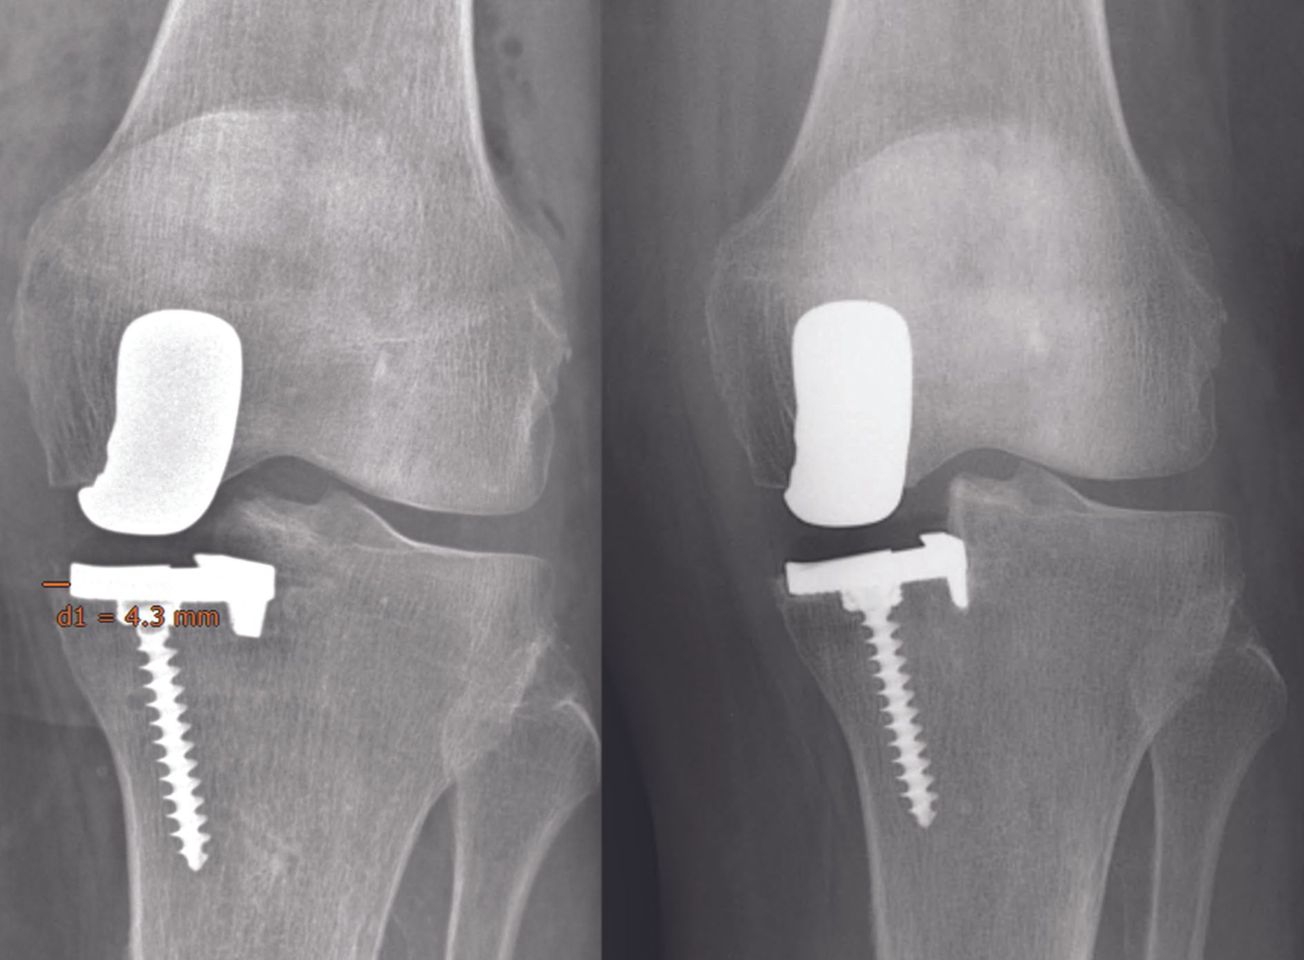

Mise au point Critères radiologiques d’une prothèse unicompartimentale réussie , Olivier Reynaud Clinique du Parc, 155 Boulevard de Stalingrad, 69006 Lyon, France N°297 - Octobre 2020 ● 17 min de lecture

19ème Journées Lyonnaises de Chirurgie du Genou - 2020 Critères radiologiques d’une UNI réussie septembre 2020